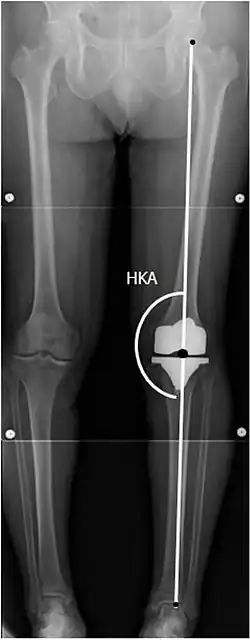

El reemplazo de rodilla se evalúa de forma rutinaria mediante rayos X, incluidas las siguientes medidas:

CRT: Ángulo cadera-rodilla-tobillo, que idealmente está entre 3° en varum y 3° en valgum desde un ángulo recto.[54] -